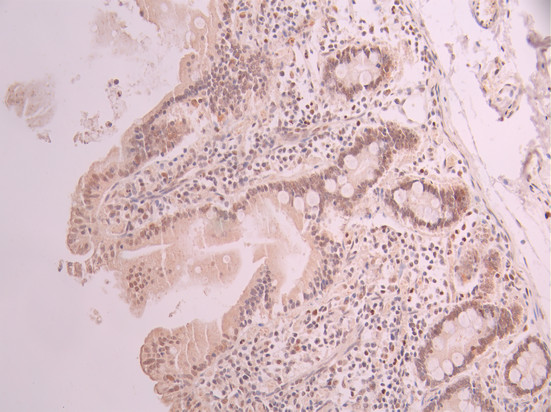

IHC image of CSB-RA799971A0HU diluted at 1:100 and staining in paraffin-embedded human small intestine tissue performed on a Leica BondTM system. After dewaxing and hydration, antigen retrieval was mediated by high pressure in a citrate buffer (pH 6.0). Section was blocked with 10% normal goat serum 30min at RT. Then primary antibody (1% BSA) was incubated at 4°C overnight. The primary is detected by a Goat anti-rabbit polymer IgG labeled by HRP and visualized using 0.05% DAB.